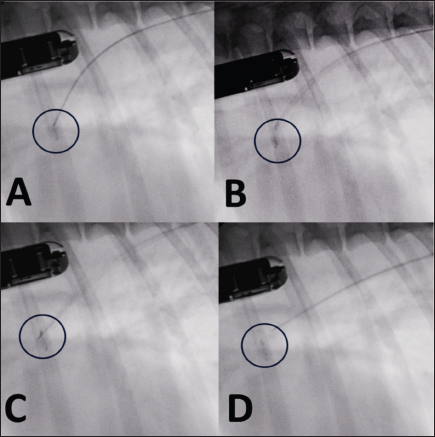

The stability of the device was subsequently tested with the push–pull “Minnesota wiggle” maneuver, and the cessation of transductal flow and the correct positioning of the device was verified using TEE (Figs. 4 and 5). The device was then deployed by rotating the delivery cable counterclockwise with the appropriate plastic vise. To verify the closure of the PDA and the absence of protrusions in the aorta further, a second angiography was performed as before (Fig. 6).

Fig. 4. Fluoroscopic sequence. (A) The first disc is deployed and the entire system is retracted until it engages the pulmonary ostium. (B) The second and third discs are released into the ampulla. (C) The device is released with anticlockwise rotation of the delivery cable. (D) The delivery catheter is removed along with the delivery cable.